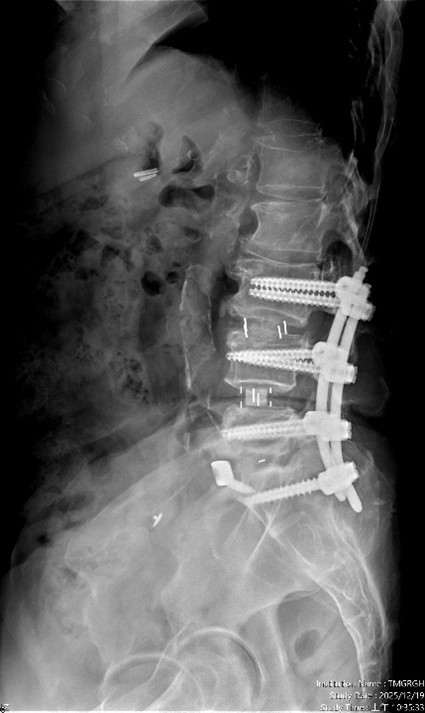

經臺中市立老人復健綜合醫院骨科部副部長林琮凱醫師詳細檢查後,診斷為第三、第四、第五腰椎合併第一薦椎的多節段脊椎狹窄,並伴隨明顯神經壓迫。醫療團隊與病患及家屬充分溝通後,決定採用「電腦導航輔助之前位/前側位脊椎融合手術」,合併後方骨釘固定,一次完成多節段融合與脊椎重建。術後病患原本的下肢痠麻與疼痛明顯改善,行走能力大幅恢復,生活品質獲得顯著提升。

相較於傳統脊椎手術需分部位、分階段進行,住院與復原時間長,臺中市立醫院引進的前位或前側位脊椎融合手術,搭配 3D 電腦導航系統,可在同一次手術中完成多節段融合與重建。手術採「間接減壓」方式,不需直接進入脊椎腔,大幅降低神經損傷風險。多數病患可於手術當日或隔日配戴背架下床行走,術後疼痛較少、恢復期明顯縮短。